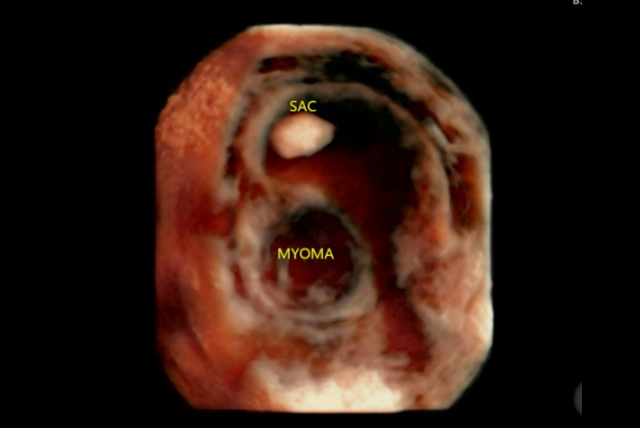

✔️ Ultrasound assessment to plan management of uterine fibroids, uterine anomalies by 2D / 3D / Power Doppler Study

✔️ Ultrasound assessment of benign and malignant endometrial pathology, vascular lesions of the uterus with Tomographic Ultrasound Imaging (TUI)

✔️ Sonosalpingography / Sonohysterography / Saline Infusion Sonography